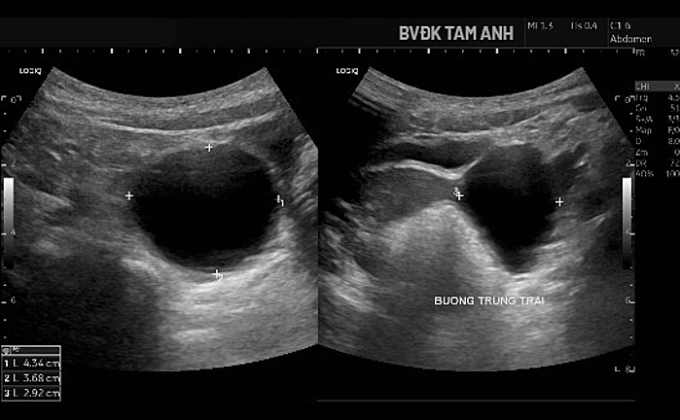

Hình siêu âm cho thấy nang buồng trứng phì đại. Ảnh: Bệnh viện Đa khoa Tâm Anh

Ngoài ngực phát triển, bé Huyền chưa xuất hiện dấu hiệu dậy thì khác. ThS.BS Đỗ Tiến Sơn, khoa Nhi, Bệnh viện Đa khoa Tâm Anh Hà Nội, ghi nhận tuyến vú của trẻ đã phát triển ở giai đoạn Tanner B3 - giai đoạn bắt đầu xuất hiện mô tuyến vú nhanh và rõ. Buồng trứng trái có nang lớn kích thước khoảng 43x37x29 mm, thành mỏng, chứa dịch trong, bên trong có nang nhỏ. Tổn thương được xếp loại ORADS 2, nguy cơ ác tính thấp. Chụp MRI xác định nang buồng trứng trái lành tính. Kết quả X-quang đánh giá tuổi xương chưa tăng, hiện phù hợp với tuổi thực của bé.